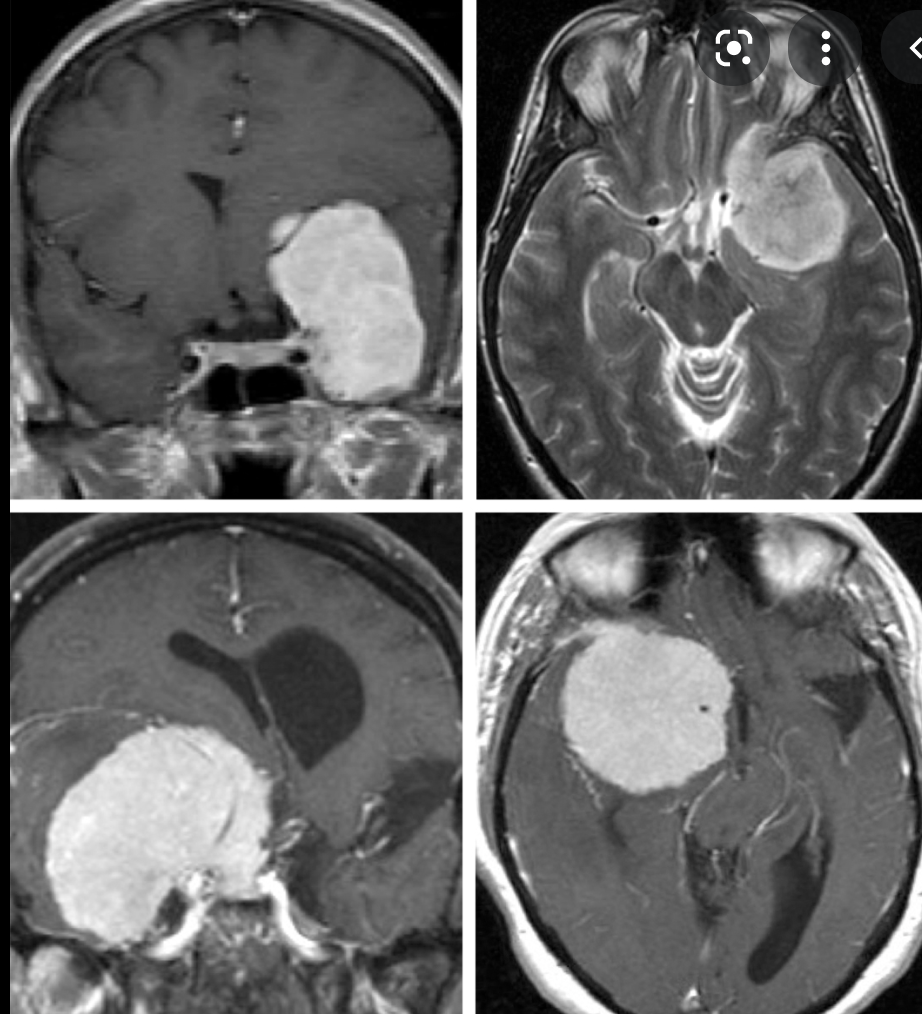

Figure 2: Medial sphenoid wing meningiomas can present different set of technical challenges based on their involvement of the medial neurovascular structures and the encasement of the carotid artery’s perforating vessels. A medial sphenoid wing meningioma with minimal medial extension is shown (upper images). The Sylvian middle cerebral artery branches drape over the superior pole of the tumor. A more true medial sphenoid wing/clinoidal meningioma with significant medial extension and encasement of the ICA is also included (lower images).